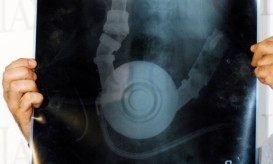

Γιατρέ μου, έχω καούρες! Το ΕΛΙΓΑΣΤ απαντά στις πιο συχνές ερωτήσεις σχετικά με το πρόβλημα

Είναι φυσιολογικό μετά από ένα γεύμα να παρουσιαστεί ρέψιμο το οποίο να συνοδεύεται από κάψιμο στο θώρακα, πίσω από...